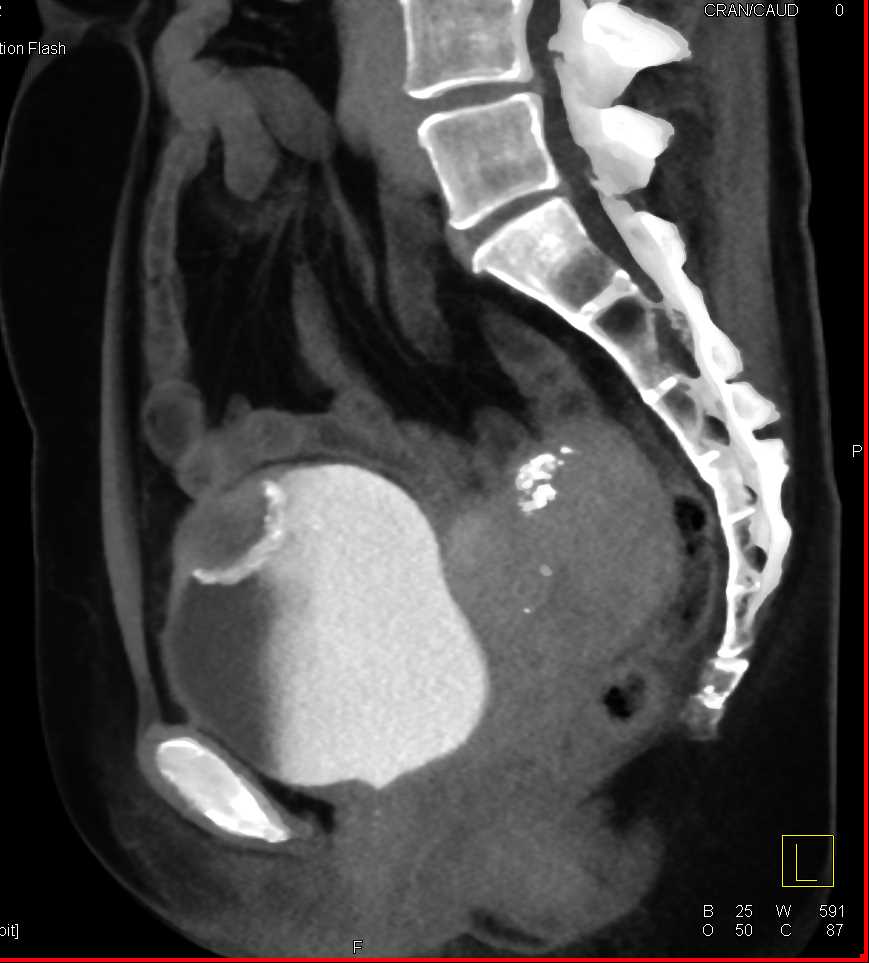

Urachal Carcinoma of the Bladder